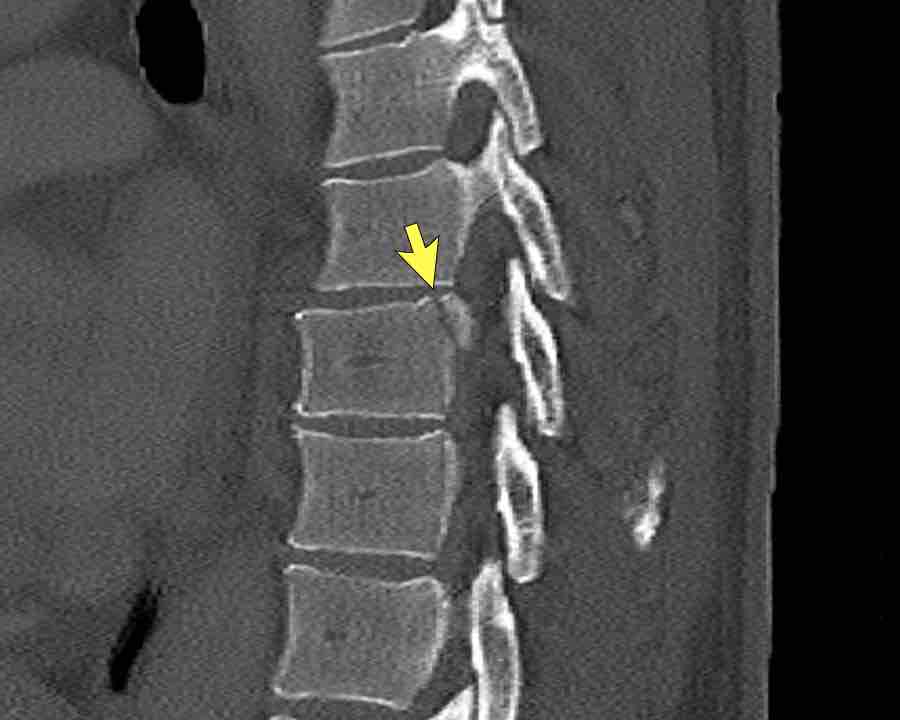

Continue with the next stack of images to classify level L2…

Scroll through images.

What is the highest AO-level?

Findings

- No dislocation ( no C type).

- Mainly horizontal fractures of spinous processus at multiple levels (B-type).

- Split fracture L2 (type A2).

Conclusion

Injury type B2 + A2 at level L2.